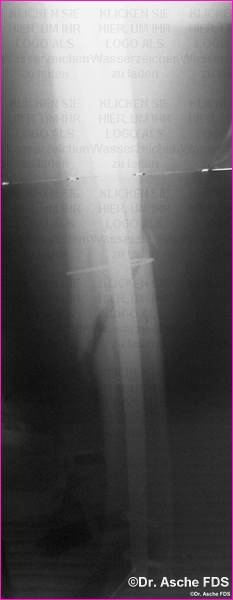

In einem Winkel von ca 20° wird schräg osteotomiert,

je nach Grad der Varisation.

Auch die Drehung spielt dabei eine Rolle. An einem Modell

muß dies vor der Operation dargestellt werden.

Dies war der Ausgangsbefund in diesem Fall (siehe Bild

oben).

13° Außendrehfehler und 10° Varusstellung |

Dreht man nun den distalen Teil des Knochens nach innen

auf der schrägen Schnittfläche, so wird nicht nur die Drehung,sondern

auch die Varusfehlstellung korrigiert.

|